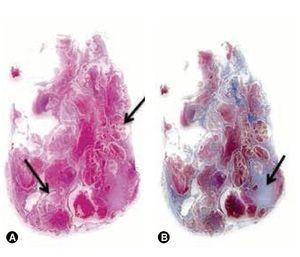

La paciente fue evaluada con una TC simple y contrastada de cráneo a su ingreso donde se observó una imagen en el atrio del ventrículo lateral izquierdo, con unas dimensiones de 31 x 37 mm en el corte axial de bordes regulares bien delimitada, heterogénea, que refuerza con el medio de contraste, se identifica un pedículo hacia el plexo coroideo ipsi-lateral, se observa aumento de la talla del ventrículo lateral izquierdo en el asta temporal y otra imagen hiperdensa formando un nivel en el mismo, diagnosticándose probable papiloma de plexos coroides (fig. 1).

Figura 1. A) Tomografía prequirúrgica de cráneo contrastada en corte axial, donde se observa lesión (flecha) atrial izquierda de bordes bien definidos, heterogénea que realza al medio de contraste y que ocasiona dilatación del atrio. B) Tomografía prequirúrgica de cráneo contrastada en corte sagital donde se observa en atrio izquierdo, lesión (flecha gruesa) de bordes bien definidos con realce al medio de contraste que depende del plexo coroideo (flecha delgada). C) Tomografía posquirúrgica inmediata de cráneo simple en corte axial, donde se observa sangrado en el lecho quirúrgico (flecha). D) Tomografía posquirúrgica inmediata de cráneo simple en corte sagital, donde se observa sangre en asta temporal (flecha delgada) y hemorragia en lecho quirúrgico (flecha gruesa), así como neumoencéfalo y hematoma subgaleal.